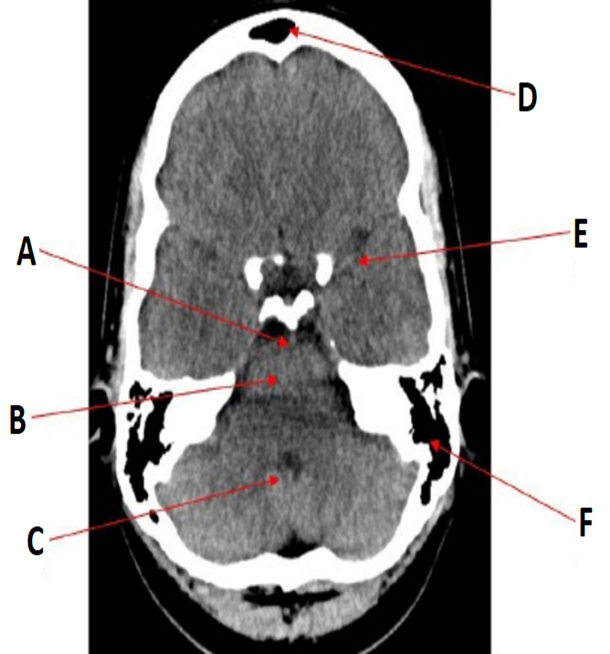

label

•A = Basilar artery

•B = Pons

•C = Fourth ventricle

•D = Frontal sinuses

•E = Middle cerebral artery

•F = Mastoid air cells